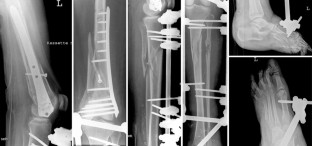

This article reports the case of a 23-year-old woman who sustained severe soft tissue injuries with open fractures of the left distal femur, the left proximal tibia, a subtotal amputation of the left foot with injuries to the anterior and posterior tibial artery due to a bomb blast. When the patient was transferred to our hospital 17 days after the trauma, all primarily closed wounds were severely infected. The fractures were treated by external fixateur and k-wire fixation. After debridement and initiation of negative pressure therapy the anterior tibial artery was reconstructed after 3 days and partial wound closure by a rectus abdominis muscle flap was achieved after 19 days. After almost total wound closure was accomplished open reduction internal fixation (ORIF) was performed for the distal femur fracture and a modification of the external fixateur for the tibial and foot fractures. The negative pressure therapy is an important component for treatment of complex soft tissue injuries and open fractures; however, it must be embedded in an interdisciplinary treatment plan with well-defined treatment goals.

Abb. 2